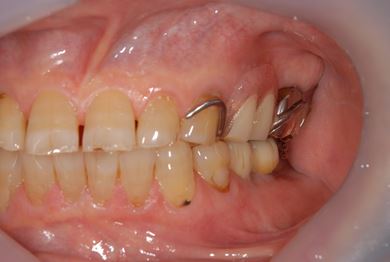

抜歯即日スピードインプラント治療+歯周外科治療

| 性別/年齢 | 男性 / 62歳 | ||||||||||||||||||||||||||||||||

| 主訴 | 左下の奥歯のブリッジがゆれて、痛みがある。 | ||||||||||||||||||||||||||||||||

| 治療方針 | 抜歯と同時にインプラント埋入を行い、治療期間を短縮する。 | ||||||||||||||||||||||||||||||||

| 治療内容 | インプラント2本(抜歯即日スピードインプラント)、ハイブリッドセラミッククラウン2本、歯周外科治療 | ||||||||||||||||||||||||||||||||

| 総治療費 | 771,960円 | ||||||||||||||||||||||||||||||||

| 治療期間 | 6ヶ月 |